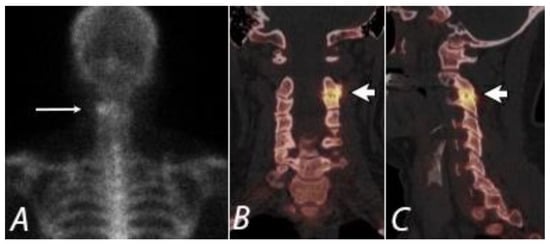

7. Knee Pain

8. SPECT/CT of Extremities